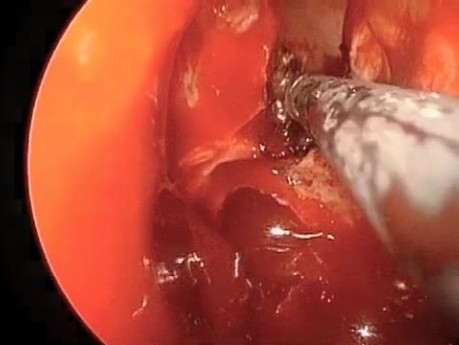

Plastyka balonowa zatoki klinowej

Wideo przedstawia nowoczesną metodę redukcji krwawienia operacyjnego - wykorzystanie balonowej plastyki zatoki klinowej zamiast tradycyjnego zabiegu.

Poszerzanie balonowe otworu zatoki w przebiegu...

Film przedstawia zabieg wykonywany w gabinecie lekarskim - poszerzanie otworu zatoki. Jest to nowa, innowacyjna metoda leczenia przewlekłego zapalenia zatok.